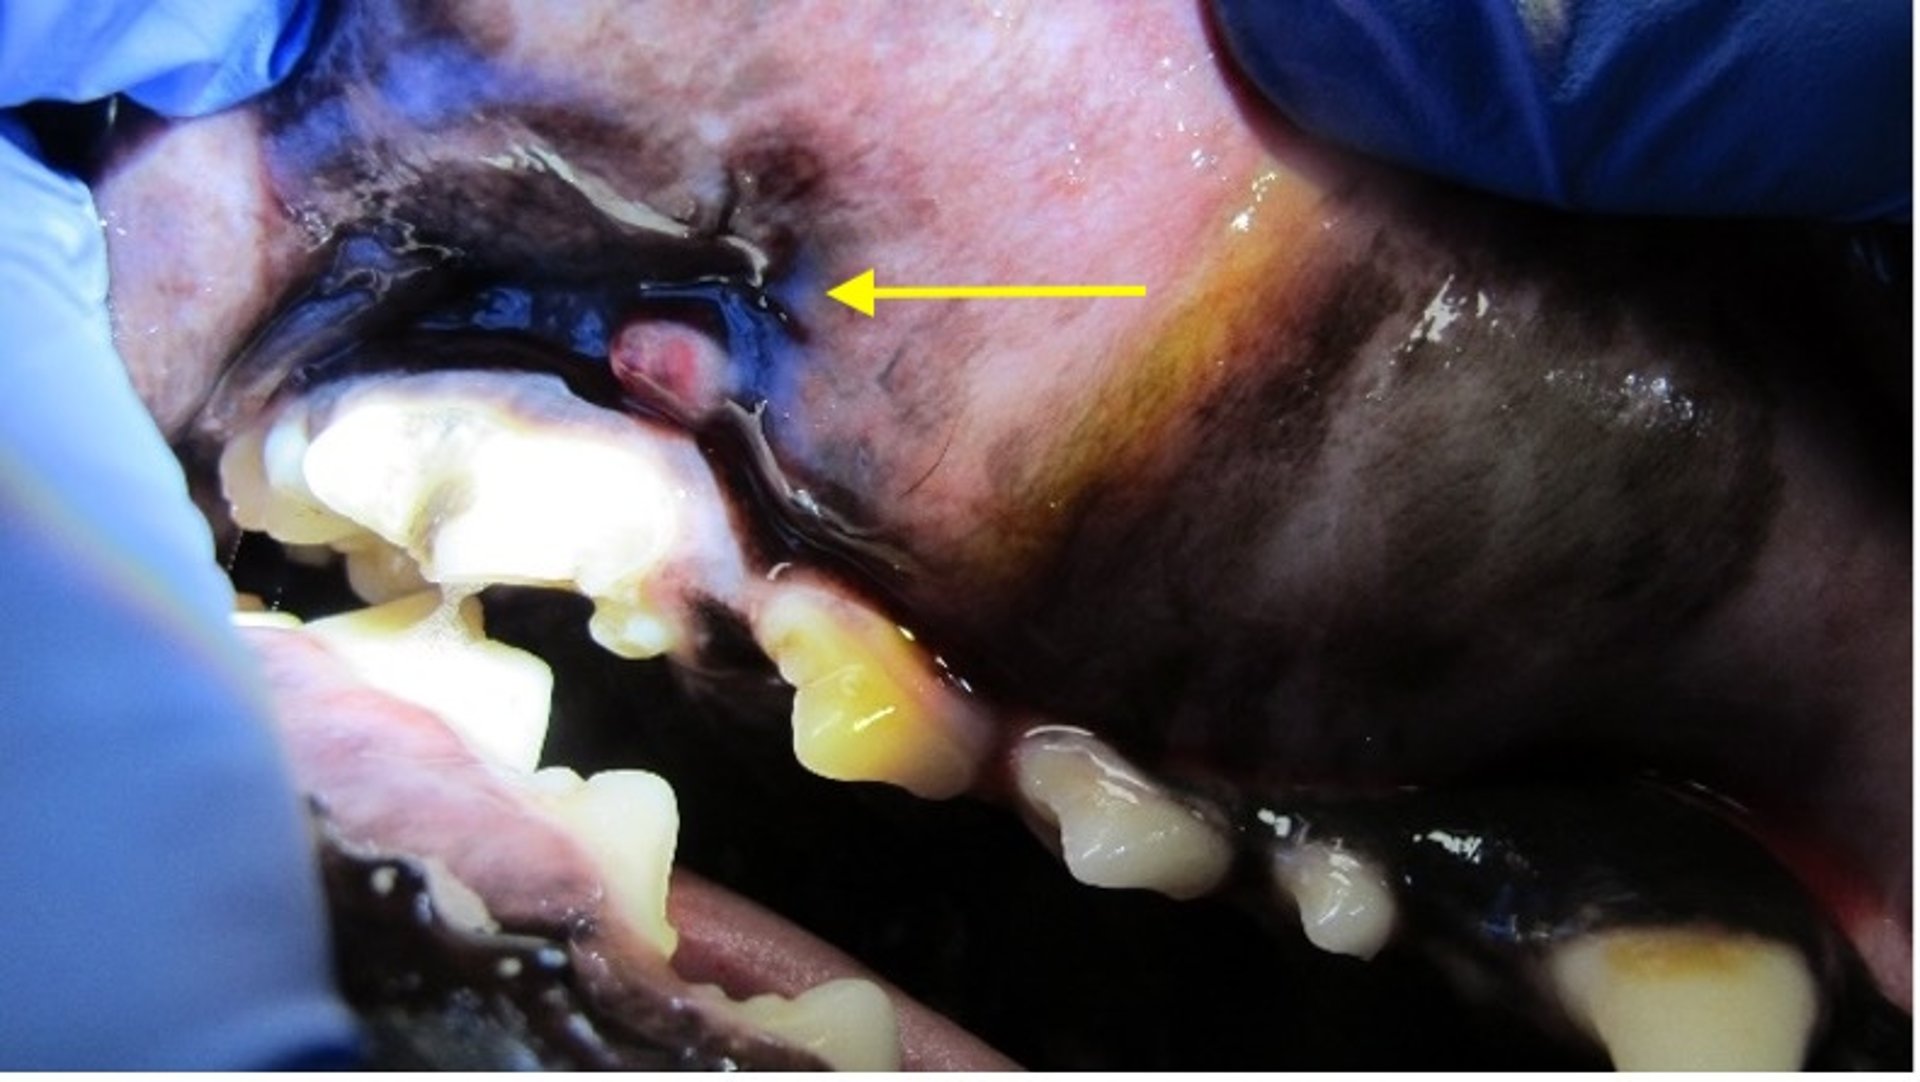

Parulis (tracto de drenaje), perro

La imagen muestra un parulis (flecha amarilla), o tracto de drenaje, asociado con un cuarto premolar maxilar derecho afectado endodóncicamente. El parulis aparece con frecuencia en la línea mucogingival.

Cortesía de la Dra. Brenda Mulherin.